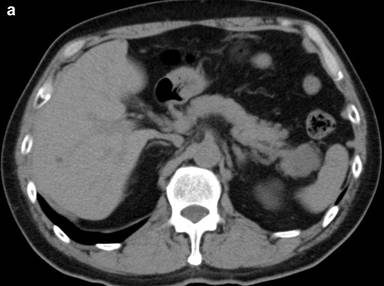

A 53-year-old man was incidentally found to have a cystic tumor in the tail of the pancreas after undergoing an abdominal ultrasound (US), which showed a 41x33 mm cystic mass in the pancreatic tail. He had no abdominal symptoms. The tumor markers, including DUPAN 2, and carbohydrate antigen 19-9, were within the normal ranges. The patient was referred to our hospital for further investigations. A contrast-enhanced CT scan (Figure 1) showed a non-enhanced cyst between the spleen and the pancreas with no solid component. Magnetic resonance cholangiopancreatography (Figure 2) revealed that the main pancreatic duct was regular and had no dilatation, and there was no communication between the cyst and the pancreatic duct. Magnetic resonance imaging (MRI) showed a lesion with a slightly high signal on a T1-weighted image; the lesion, which was well circumscribed, was in the tail of the pancreas (Figure 3). MRI on a T2-weighted image also showed the lesion with a high signal. The cystic tumor was negatively visualized on the PET image. Endoscopic ultrasound (EUS) was performed, which showed a 55x31 mm pancreatic tail lesion with a solid and cystic mixed component (Figure 4a). An endoscopic ultrasound-guided fine-needle aspiration biopsy in a trans-gastric approach of this lesion suggested a diagnosis of a benign squamous cyst (Figure 4b).

Figure 1. a. Abdominal computed tomography (CT) findings showing a 41x33 mm cyst between the spleen and the pancreas. b. Contrast-enhanced CT findings showing a nonenhanced cyst. The solid component was not recognized. The cyst is close to the splenic hilum. |